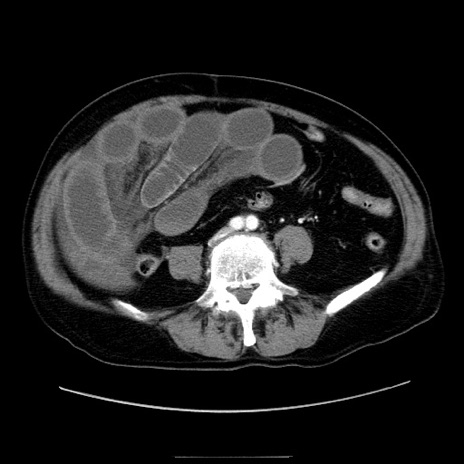

症例30(横断像)

【症例】80歳代男性

【主訴】臍周囲痛

【現病歴】約6時間前から臍下部痛が出現。次第に腹部膨隆・背部痛も生じてきたため来院。背部痛の場所は変化しない。

【既往歴】腎盂腎炎

【身体所見】意識清明、BT 36.3℃、BP  131/87mmHg、P 87bpm、SpO2 100%(RA)、臍周囲自発痛・圧痛あり、反跳痛なし、自発痛部位に一致して板状硬あり、腹部膨隆、腸雑音減弱、CVA tenderness両側陰性。

【データ】WBC 19600、CRP 0.33